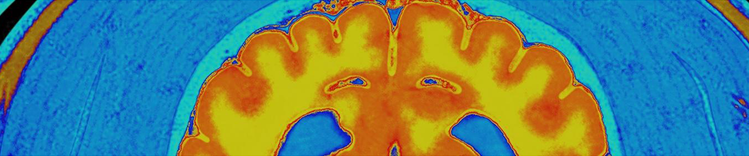

BRAIN MRI

Changes in the aging brain

Physical changes in the brain associated with aging include:

- Atrophy (shrinkage) of tissue in some regions

- Increased ventricular volume

- Loss of neurons and synapses and reduced formation of new neurons

- Accumulation of abnormal proteins